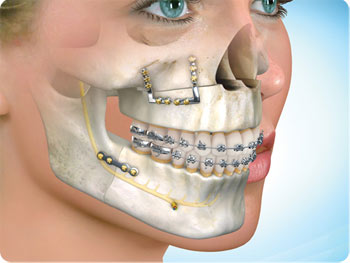

Ortodontiyle dişlerin yeniden konumlandırılması mümkün olduğu gibi ortognatik cerrahi ile de büyüme gelişimlerini tamamlamış erişkin hastalarda ki çene uyumsuzlukları düzeltilebilmekte, çiğneme, konuşma, soluk alma fonksiyonları iyileştirildiği gibi yüz görünümü de güzelleştirilebilmektedir.

Cerrahi öncesi 6-18 ay süreyle orthodontik hazırlık aşaması gerekmektedir. Bu aşamada dişlerinizin daha da kötüleştiğini düşünebilirsiniz fakat dişlerinizin konumları çenelerinizin ameliyat sonrasındaki konumlarına göre şekillenmektedir. Cerrahi sonrası çeneleriniz uygun konumlarına getirildiğinde dişlerinizin muntazam ilişkide olduklarını göreceksiniz.

Son görüntüleme teknikleri kullanılarak ortognatik tedavi sonucu kişinin kazanacağı estetik ve fonksiyonel faydalar öngörülebilmektedir. Bilgisayar destekli tedavi planlaması ve diğer teknolojik gelişmeler, cerrahi işlemin etkinliğini artırmakta ve cerrahi sonrası iyileşme sürecini kısaltmaktadır. Böylece hastalar cerrahi sonrası rutin hayatlarına en kısa zamanda dönebilmektedirler.

Cerrahi işlem hastane ortamında, genel anestezi altında, çene cerrahisi uzmanı ve ekibi tarafından gerçekleştirilmekte ve gereken işlemin tipine bağlı olarak birkaç saat sürebilmektedir. İşlem sonrası 2 hafta içinde okul ya da işinize dönebilirsiniz. İşlemden sonra gereken iyileşme süresi sonunda (yaklaşık 4-8 hafta), ortodontistiniz kapanış ilişkinizi mükemmelleştirmek için ortodontik tedavinize devam edecektir. Çoğu vakada, braketleriniz cerrahi sonrası 6-12 ay içinde çıkartılmaktadır.